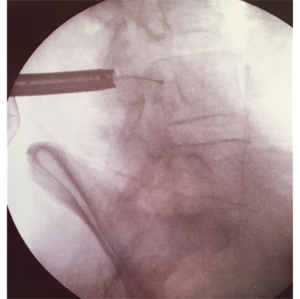

Imatge de Rxintra-operatòria mostrant la cànula endoscòpica (esquerra) de la qual sobresurt l’elèctrode de radiofreqüència (amb una boleta en el seu extrem) creuant el canal medul·lar. Això confirma que hi ha prou espai en el canal vertebral, confirmant l’alliberament de la medul·la després de la descompressió endoscòpica.